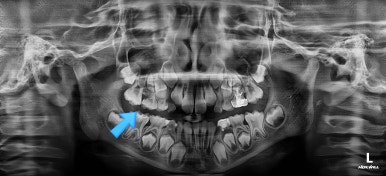

부산어린이치아교정 키다리아저씨치과에 처음 내원하셨을 당시의 X-ray 사진입니다.

이 때는 7세 3개월 때였습니다.

보통 만 6세 부터 아래 앞니 부터 영구치가 나기 시작하며, 비슷한 시기에 유치보다 더 뒤에 영구치 어금니가 나오게 됩니다.

이번 환자분은 제 나이보다는 치아나이가 어린편이어서 다른 부위의 어금니도 나오지 않았긴 하지만 치과 검진에서 우연히 해당부위(화살표)의 치아가 문제가 있음을 발견하셨던 경우입니다.

만 6세 이후 반드시 X-ray 찍어보시기를 추천드립니다.